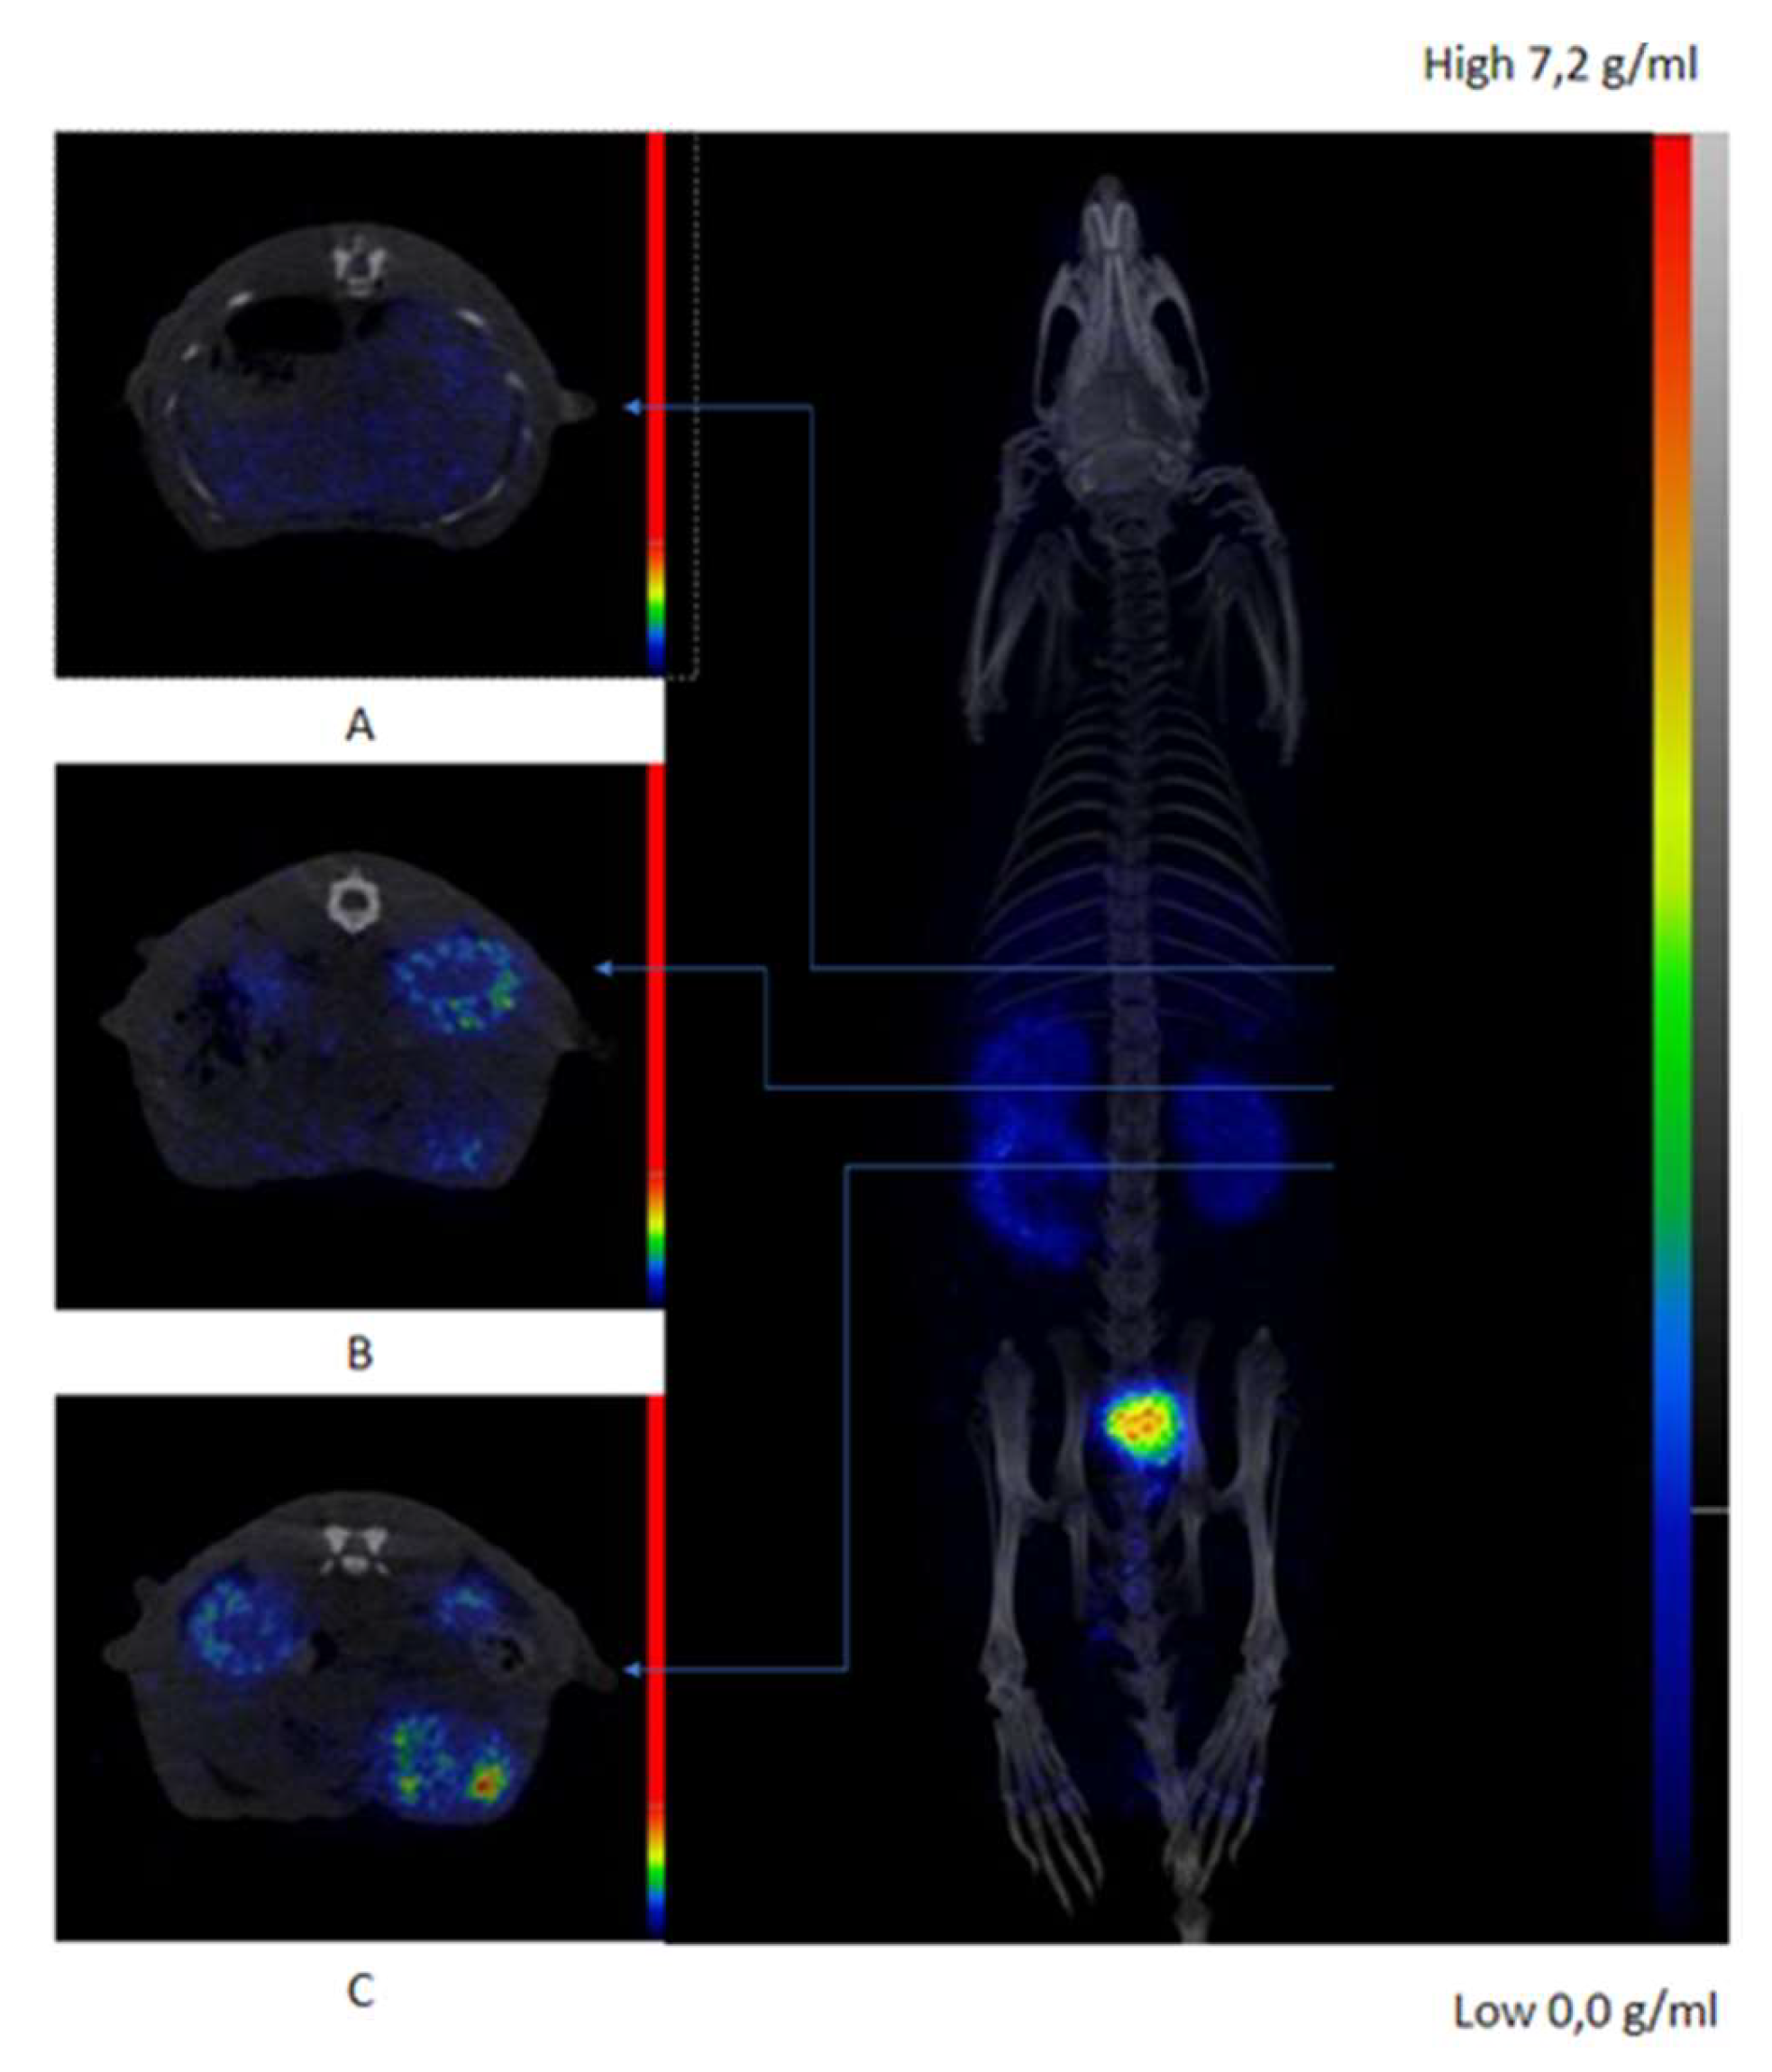

2.5. In Vivo Evaluation and Ex-Vivo Biodistribution

4.2.8. Ex-Vivo Biodistribution